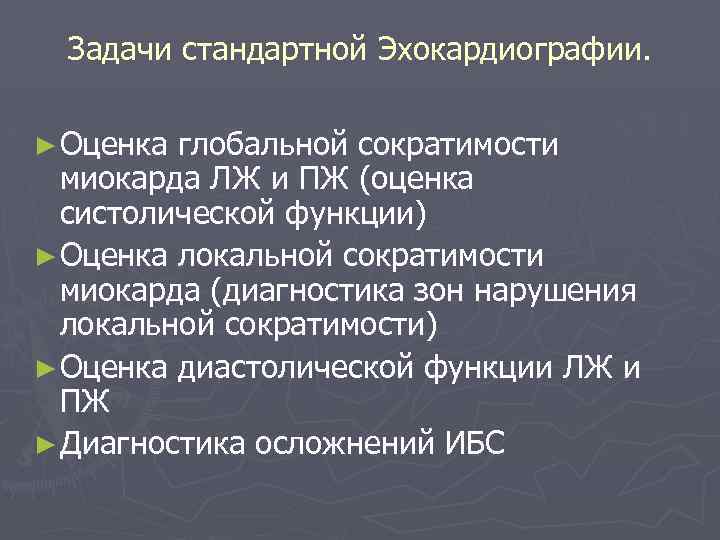

Задачи стандартной Эхокардиографии. ► Оценка глобальной сократимости миокарда ЛЖ и ПЖ (оценка систолической функции) ► Оценка локальной сократимости миокарда (диагностика зон нарушения локальной сократимости) ► Оценка диастолической функции ЛЖ и ПЖ ► Диагностика осложнений ИБС